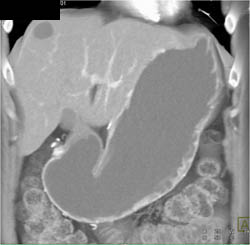

Gastric Cancer With Perigastric Spread in 3D